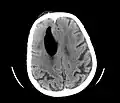

Additional images

-

Large pneumocephaly secondary to surgical wound -

Pneumocephaly